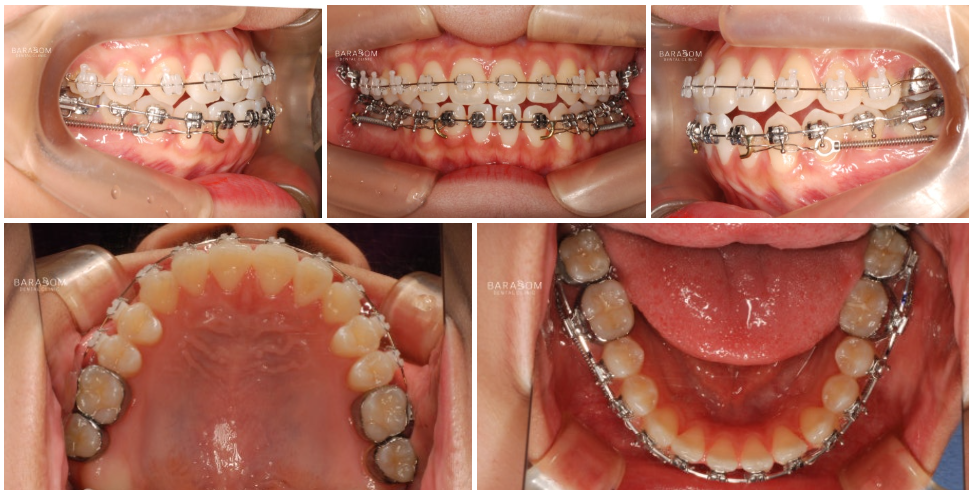

| 종결

치료를 받은 지 17개월 가량이 지난 후 모습입니다.

1️⃣반대 및 절단 교합 양상이

모두 해소되었으며,

2️⃣골격적인 문제의 한계를 넘어

아랫턱과 윗턱이 조화를

이루는 모습이 관찰됩니다.

또한 윗니가 아랫니를 덮으며

정상적인 피개량을 가지고 있는데요,

하악 전체 치열 후방 이동과

상악 앞니의 정출을 통해

교합의 안정과 함께

심미를 되찾은 모습입니다.